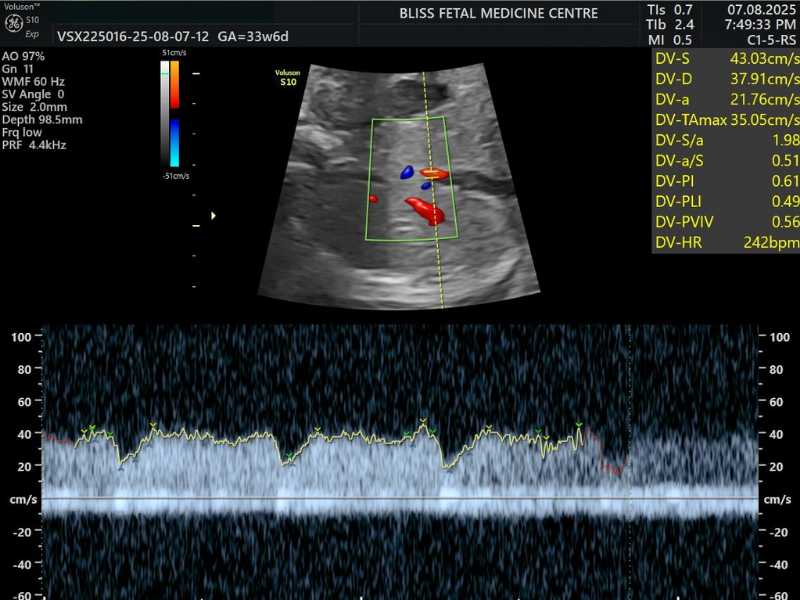

8. Fetal Colour Doppler + Biophysical Profile

Unlike standard Doppler scans, Fetal Colour Doppler converts sound waves into colour images to provide a clearer view of blood flow in the placenta and uterus. On the other hand, the Biophysical Profile (BPP) helps assess the health of the fetus via fetal heart rate monitoring and ultrasound.

When Is It Performed?

- It is performed between 28 and 32 weeks in the third trimester.

- It is needed to assess the blood flow, heartbeat and overall well-being of the baby.

- It is also needed to monitor uneven growth patterns in twins or multiple fetuses.